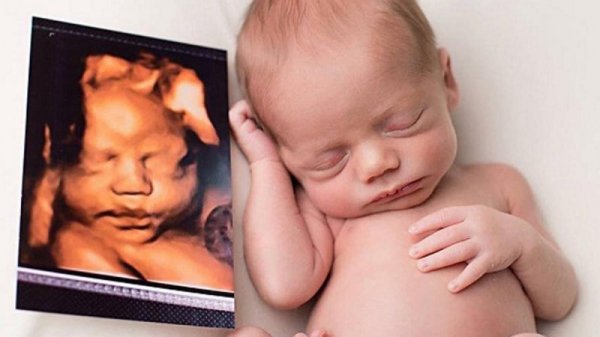

Mang thai 3 tháng đầu có nên siêu âm nhiều không? – Bố mẹ chỉ nên đi khám thai, siêu âm thai định kỳ theo những mốc quan trọng của thai nhi. (ảnh: eva.vn)

Tuy nhiên, theo như các chuyên gia y tế cho biết, khi thai nhi được dưới 10 tuần tuổi thì không nên đi siêu âm màu nhiều, không quá lạm dụng khi không thật sự cần thiết. Bởi loại siêu âm này có tác dụng nhiệt, có ảnh hưởng nhất định đến quá trình hình thành nên các hệ cơ quan quan trọng của thai nhi. Mặt khác, khi lạm dụng siêu âm trong khám thai sẽ gây ảnh hưởng đến tâm lý của mẹ, có thể sẽ xảy ra rủi ro khi di chuyển đến phòng khám. Không những vậy, siêu âm quá nhiều còn lãng phí thời gian và tiền bạc của bố mẹ. Đây cũng chính là lời giải đáp cho câu hỏi của những mẹ mới mang bầu, mang thai 3 tháng đầu có nên siêu âm nhiều?